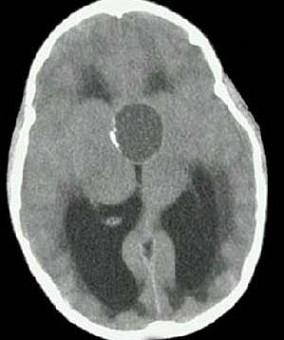

问题 女,38岁,闭经、嗜睡、尿多、视物模糊半年,精神烦躁,CT、MRI检查如图,最可能的诊断为()

选项 A.颅咽管瘤 B.脑膜瘤 C.蛛网膜囊肿 D.垂体瘤 E.表皮样囊肿

答案 A